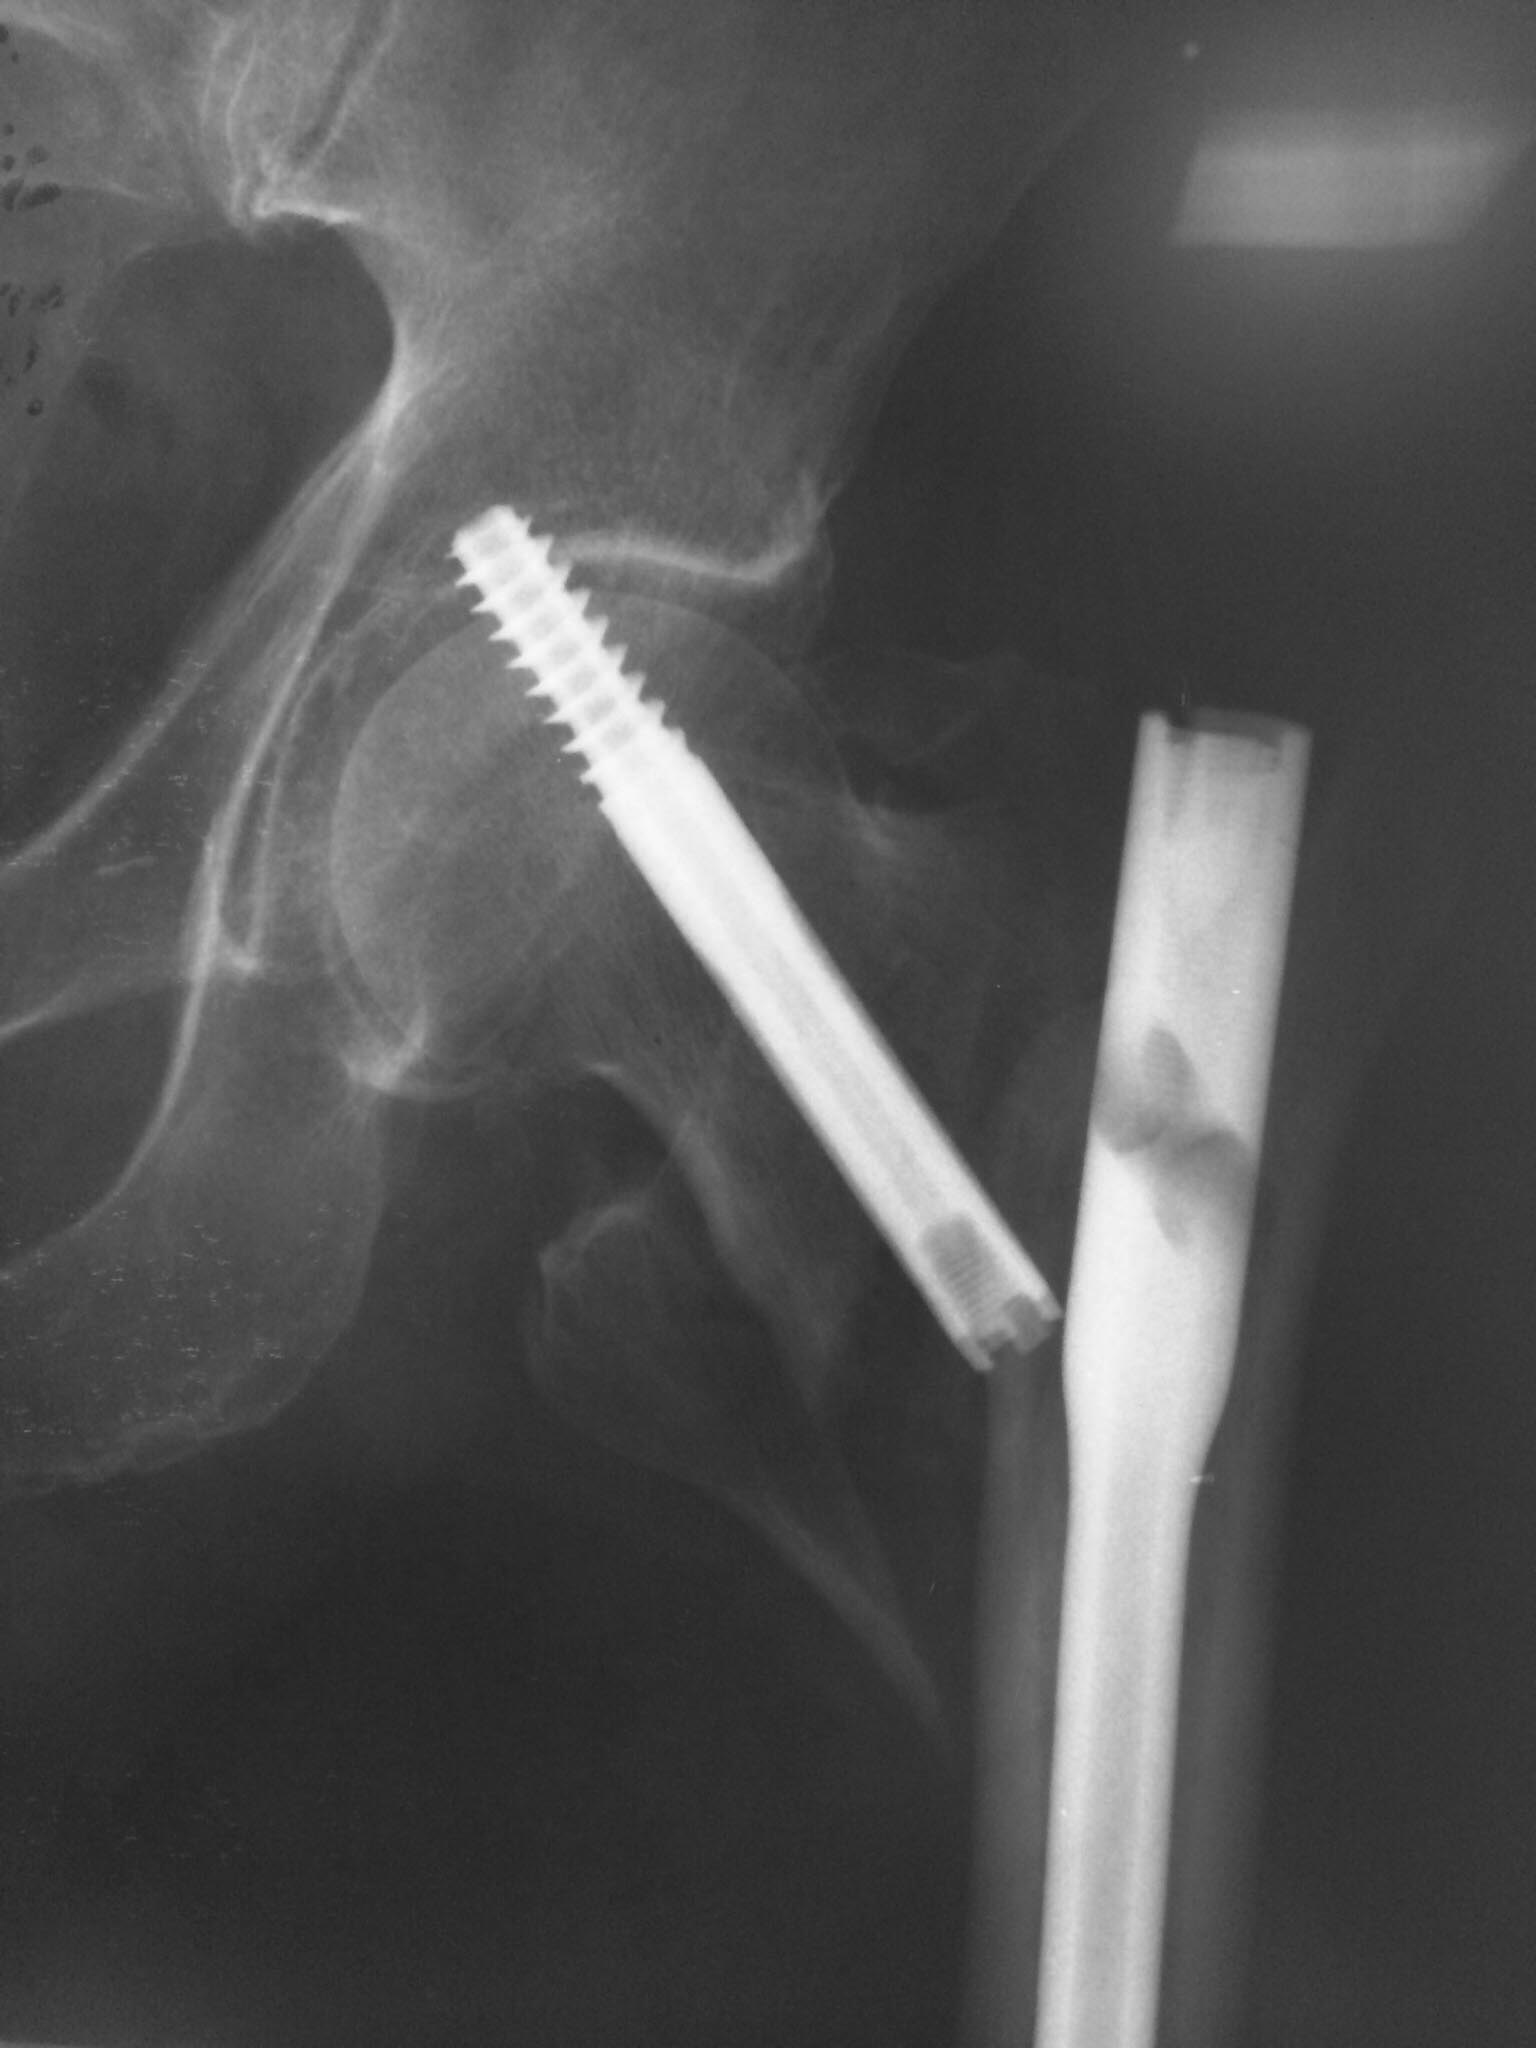

А зачем копья ломать?. Вы настроены на эндопротезирование? Так она

протез вывихнет по любому, учитывая парез. Значит, либо PFN либо гамма.

В гамме шеечный винт блокируется. Поэтому я бы выбрал гамму или любой

интрамедуллярый гвоздь с возвожностью блокировать шеечный винт. Пусть

вариант PFN, но с одним винтом и заблокировать его. Что бы не было как в

приложении.( там в китайском гвозде заклинило блокирующий винт и шеечный

винт не заблокировался)